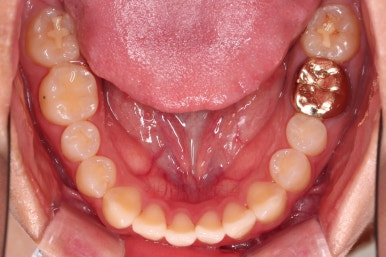

1. 처음 내원 시의 입안의 모습

부산치아교정잘하는곳 키다리아저씨치과에 처음 내원하셨을 당시의 입안 모습입니다.

얼핏 보면 많이 삐뚤어지지는 않은 편인데, 눈에 바로 띄는 앞니가 뻗쳐 있으면서 획 돌아있는데요. 정렬이 필요한 상황이었습니다.

어금니쪽은 많이 삐뚠 편은 아니었으며, 윗니 앞니가 많이 앞으로 뻗쳐 있는 상태였습니다.

아까 말씀 드렸던, 왜 윗니 앞니만 뻗칠까?에 대한 대답은 "주걱턱의 골격구조를 가지셔서" 입니다.

아래턱이 앞으로 나오면 나올수록 윗니는 앞에 있는 아래턱과 만나기 위해 앞으로 뻗치는거죠.

그렇다면 뻗친 앞니를 수직으로 세워주기 위한 전제조건은? 당연히 아랫니가 뒤로 들어가야 합니다.